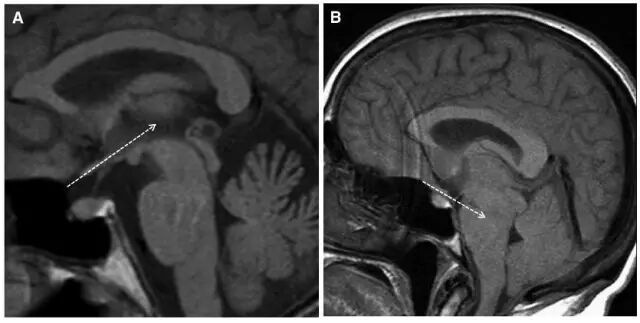

患者,男,40岁;因不明原因反复头痛并加重2月,于2017年4月21日当地医院头颅CT、MRI提示:双侧额颞顶部慢性硬膜下血肿收住院(图1)。并于4月24日行“左侧慢性硬膜下血肿钻孔引流术”。术后患者卧床、静脉补液,头痛症状有所缓解。复查头颅CT显示左侧血肿较前减少,但右侧稍增大(图2)。

图1. 第一次术前CT及MRI显示双侧慢性硬膜下血肿,中线稍右偏。

但术后2天再次出现头痛,不能缓解,5月2日复查头颅MRI提示硬膜下血肿术后复发,伴小脑下坠,脑沟及小脑上方仍可见较多脑脊液,四脑室变小,颅内静脉系统扩张明显(箭头所示见横窦扩张)(图3)。

图3. 术后1周(5月2日)复查头颅MRI显示左侧硬膜下血肿术后复发,伴小脑下坠,脑沟及小脑上方仍可见较多脑脊液,四脑室变小,颅内静脉系统扩张明显(箭头所示见横窦扩张)。